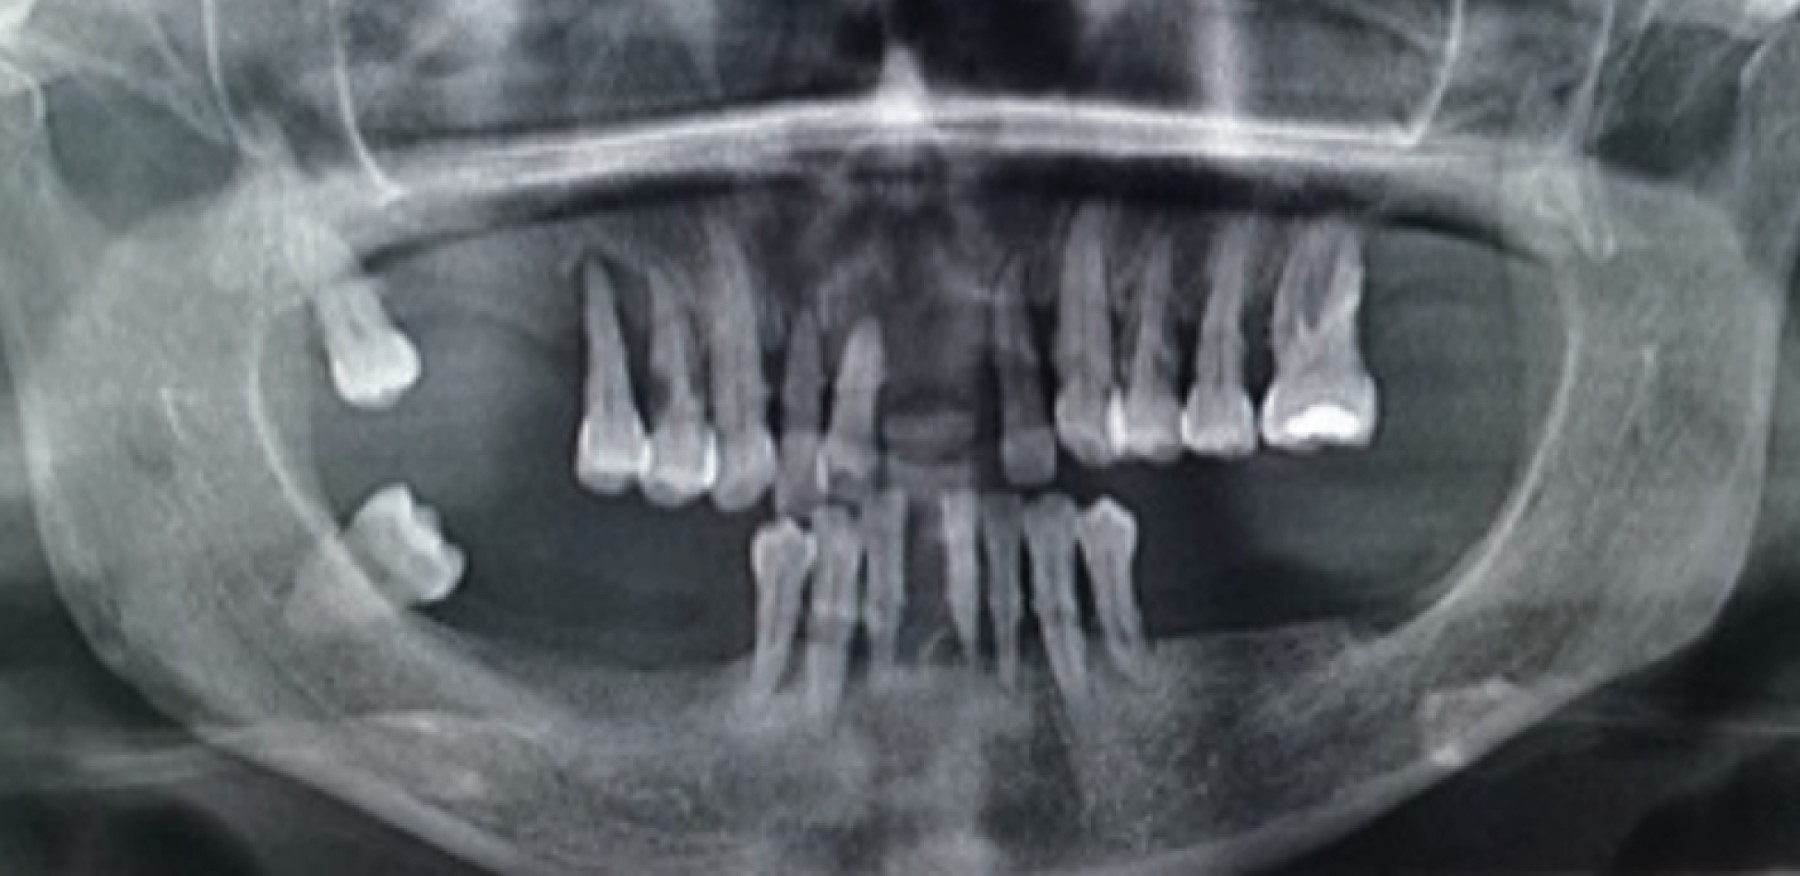

En el análisis radiográfico se observa una pérdida ósea entre 60 y 90% casi de forma generalizada, el diente 18 y 48 completamente mesializado (Figura 3).

Figura 3